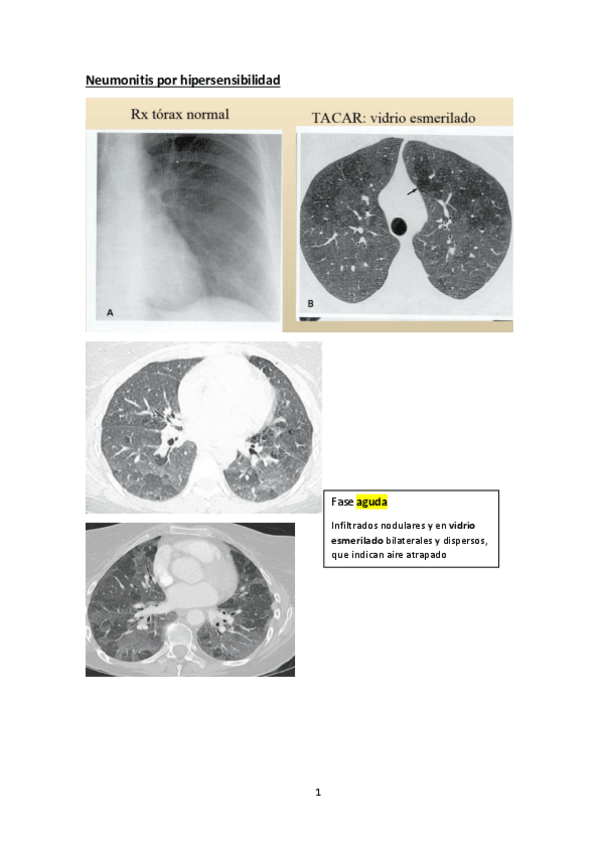

He publicado nuevos apuntes de 4º Enfermedades del Aparato Respiratorio: NEUMONITIS.pdf

5 páginas

He publicado nuevos apuntes de 4º Enfermedades del Aparato Respiratorio: Respiratorio-Anexo-T11.pdf